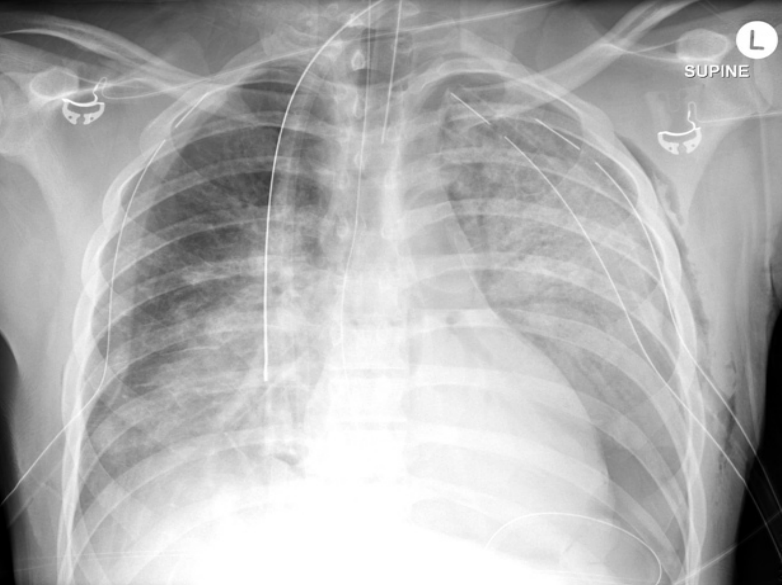

AP chest X-ray (critically ill patient and intubated)

tracheal intubation (above the carnia. if lower it will inter right main stem bronchous→leads ti left lung collaps)

NG tube

Central line (into SVC)

left main stem bronchous showing radio-opacity and patent bronchioles→Air broncho-grams (if localised→indicates infectious process)

Bilateral diffuse lung opacities on both lung fields (slightly more on left side)

Ddx: ARDs, decomensated heart failure, aspiration

Air bronchograms